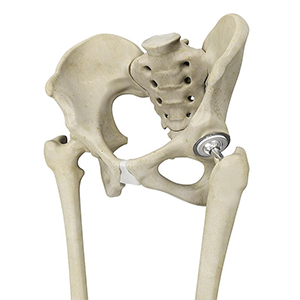

Revision Hip Replacement

Revision hip replacement is a complex surgical procedure in which all or part of a previously implanted hip joint is replaced with a new artificial hip joint.

Primary hip replacement or hip arthroplasty is a surgical procedure in which the worn out or damaged parts of the hip joint are removed and replaced with artificial components called prostheses or implants that are made of metal, plastic, or ceramic.